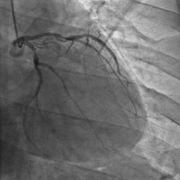

冠状动脉造影手术过程- 5.0共8页

- 冠状动脉造影手术过程,一,冠脉造影的适应症冠脉造影的主要目的是明确有无冠状动脉疾病,选择治疗方案和判断预后,有心绞痛症状的患者,尤其是药物治疗无效或者通过无创检查发现有高危因素的患者应行冠状动脉造影术,对拟形瓣膜性心脏病或先天性心脏病手术的